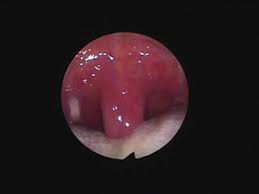

觀察口腔內部也能獲得有效情報。大大張開嘴巴時應該可以清楚看到整個懸壅垂,但是當舌頭太大時,懸壅垂就會變得難以清楚看到。單純性打呼症的人通常懸壅垂可以清楚看到,但是睡眠呼吸中止症的患者懸壅垂則部分被隱蓋,變得難以窺視全貌。